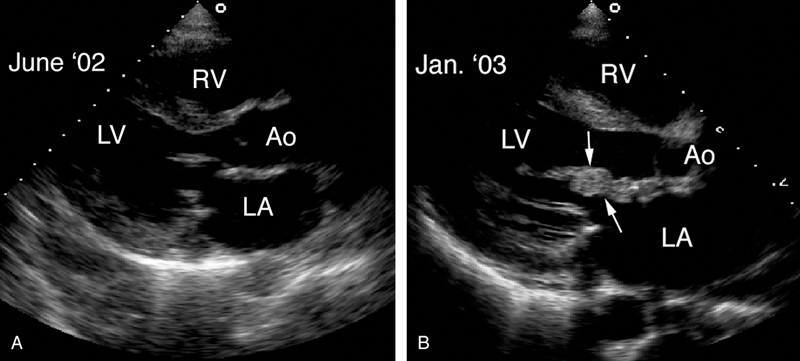

فحوصات تشخيصية لبعض امراض القلب والشرايين التاجية